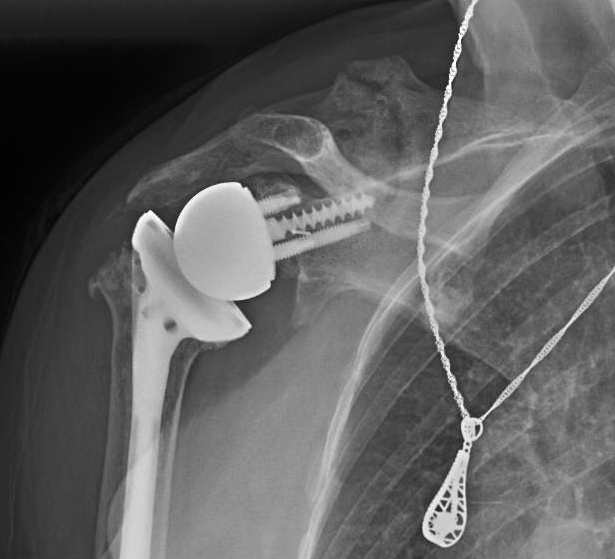

Operation 4. This failed and the humeral component was revised to a CTA head. Five years later she had painful dysfunctional shoulder she had these radiographs and pseudoparalysis of her shoulder.

Operation 5. This was revised to a reverse total shoulder

Four months later she developed pain in the back of her shoulder. Radiographs showed a fatigue fracture of her scapular spine (see arrow in the x-ray below).